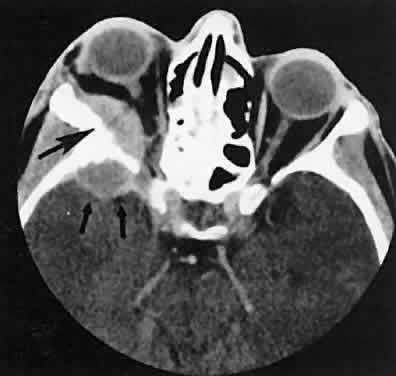

Fig. 3. Axial view showing a dilated superior ophthalmic vein (SOV; arrows) secondary to dural-cavernous sinus fistula. Note the normal-sized SOV in the contralateral orbit.